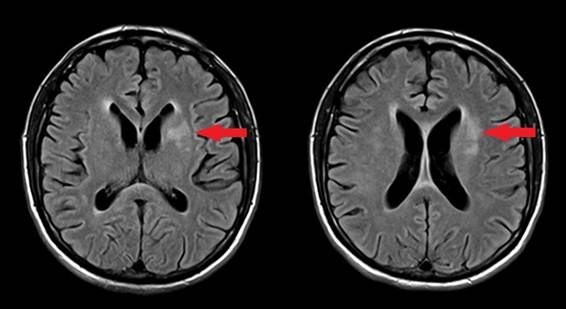

Resonancia nuclear magnética (RNM) de cráneo: aumento de la señal en T2 y Flair a nivel ganglio basal y esplenio del cuerpo calloso, sin restricción ni realce en la difusión sugestivo de proceso infeccioso. No se realizó espectrometría (Figura 1).

RNM de cráneo: Hiperintensidad en T2 y FLAIR que compromete ambos hemisferios cerebelosos, lóbulo temporal y frontal izquierdo, occipital derecho y gangliobasal bilateral. Realce nodular a nivel gangliobasal bilateral. Discreto realce ependimario. No se realizó espectometria (Figura 2).

Aunque los hallazgos en la TC y RNM de cráneo poseen baja sensibilidad y especificidad para el diagnóstico de encefalitis a CMV, se han descripto imágenes que podrían sugerir la infección en un contexto clínico adecuado.

Las imágenes que pueden observarse en la RNM corresponden a ventriculitis con lesiones sub-ependimariashiperintensas en T2 y FLAIR conrealce periférico lo que sugiere la “imagen en ojo de búho; alteraciones en la sustancia blanca con nódulos (hipo intensos en T1 ehiperintensos en T2), leucopatía difusa, atrofia focal y masa focal nodular. En este estudio adquiere importancia la técnica de difusión, las presencias de manchas brillantes con restricción en la difusión con tropismo ventricular son sugestivas de encefalitis por CMV. 16LaRNM puede evidenciar aumento focal o difuso de la señal en T2 y FLAIRa predominio de la sustancia blanca periventricular.Es característico el realce ependimario y meníngeo tras la administración de gadolinio.1,2,6,9,10,12-15En la tabla 1 se resumen los principales hallazgos imagenológicos encontrados en nuestros tres casos, todos descritos en la literatura.

Es claro que, de los estudios de imagen la RNM constituye la técnica de elección.